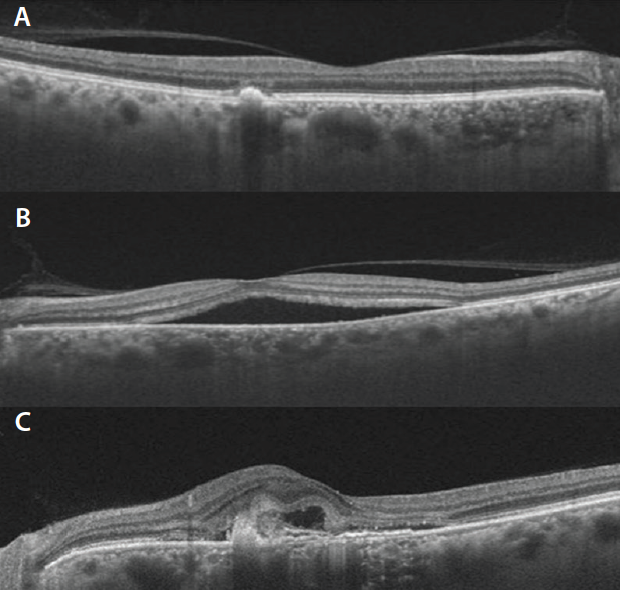

Figure 6. Rendered infrared image (A) and SS-OCT scan (B) of a patient with thickened choroid and multiple hyperreflective foci in the choroid. Subretinal fluid, double layer sign, and notched pigment epithelial detachment can also be observed.

Choroidal Hyperreflective Foci

Choroidal hyperreflective foci have been described in many chorioretinal pathologies, including Stargardt disease, RP, and CSCR (Figure 6).52-54 The mechanism that has been proposed for their formation is the loss of photoreceptors, with migration of RPE cells within the choroid. The number of hyperreflective foci tends to increase with disease severity.52